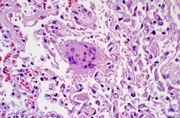

Американские ученые из Национального института аллергологии и инфекционных заболеваний сообщили об успешном завершении работ по созданию вакцины против атипичной пневмонии (SARS). Сейчас разработанный ими препарат готовится к клиническим испытаниям. Разработанная учеными вакцина представляет собой суспензию фрагментов вируса атипичной пневмонии. В отличие от аналогичных препаратов, она вводится не внутривенно или внутримышечно, а назально, в виде специального спрея. Соответственно, вакцина оказывает максимальный эффект в дыхательных путях, являющихся «входными воротами» для SARS, и практически не действует на уровне всего организма.